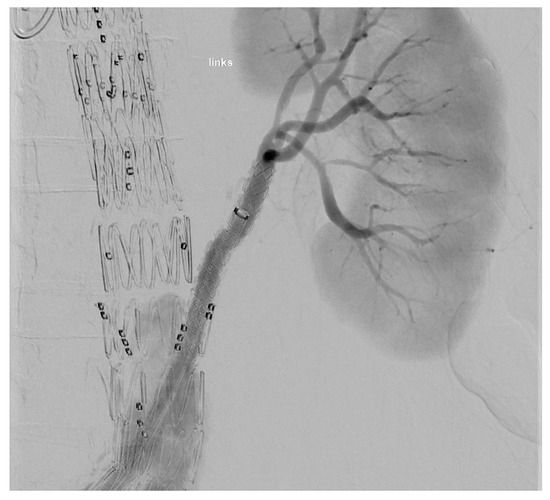

The target vessel of the upward-facing branch was always at least one of the renal arteries (Figure 2). In two cases, both renal arteries were connected through upward-facing branches, and in one case, we used it for an accessory renal artery.

At the end of every operation, an angiography was performed to obtain an overview regarding if the BSGs are patent and if there is any sign of an endoleak of any type (Figure 3 and Figure 4).

Figure 3. Upward-facing branch for the LRA.

Figure 4. Result of a procedure.